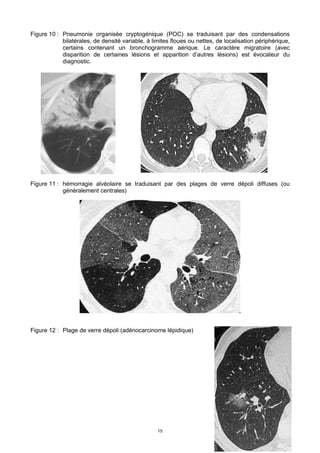

Figure 4 : Miliaire tuberculeuse : micronodules (< 3 mm) à contours nets, de distribution diffuse

dans le parenchyme pulmonaire. De gauche à droite et de haut en bas : radiographie

de thorax, même cliché, zoom sur le lobe inf droit , scanner thoracique, coupe en

fenêtre parenchymateuse ; comparaison au même niveau de coupe d’un poumon droit

normal avec et l’aspect de la miliaire de ce patient

Figure 5 : Métastases pulmonaires d’un cancer thyroïdien : nodules à contours nets (on note

aussi l’existence d’un épanchement pleural droit).